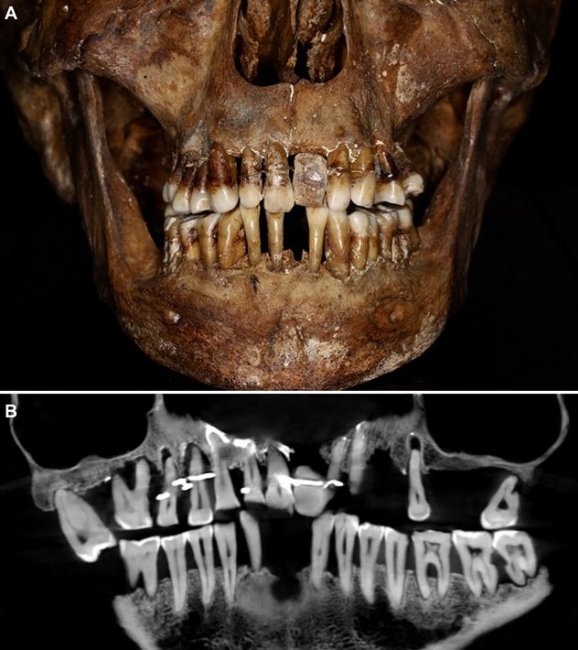

Отличным примером тогдашних протезов служат останки Анны д'Алегри, которая умерла в 1619 году и была забальзамирована и похоронена в свинцовом гробу. Их обнаружили еще в 1988 году при раскопках в замке Лаваль, и археологи сразу обратили внимание на нестандартное строение, а также очень хорошее качество ее зубов. Но тогда не было технологий для их изучения, а сегодня при помощи 3D-рентгенографии мы можем узнать секрет д'Алегри.

Исследования останков Анны д'Алегри показали, что ее зубы были стянуты и скреплены золотой проволокой. Также у нее был искусственный зуб из слоновой кости, а не клыка гиппопотама, как было модно в те времена. Увы, у технологии был крупный недостаток – натяжение проволоки ослабевало со временем и ее приходилось подкручивать, что плохо влияло на соседние зубы. И, тем не менее, она сохранила отменную улыбку до самой своей смерти в возрасте 54 лет.